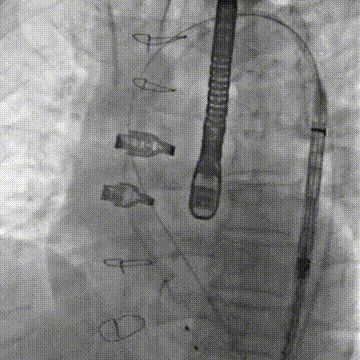

患者在全麻下进行手术,经右侧股动脉建立主入路,直头导丝跨瓣后交换预塑弯形导丝放置于左室。TaurusMax®经导管主动脉瓣系统装载AV29瓣膜,该系统具有“双轴”调弯功能,系统过弓跨瓣更加安全顺畅,同时系统在跨瓣后可实现同轴调整,降低术中对导丝操作的依赖,改善瓣膜释放不同轴导致的高低瓣问题,提升瓣膜释放稳定性及血流动力学。瓣膜在调弯状态下一次释放脱钩,瓣膜深度瓣下2mm,形态良好,同轴性佳,DSA下对合缘对齐(CA)结果良好。

调弯过弓并跨瓣

跨瓣后T-Marker方向检查

通过显影点初步判断CA&辅助判断深度

跨瓣后同轴调整

同轴调整前后对比

调弯状态下稳定脱钩释放